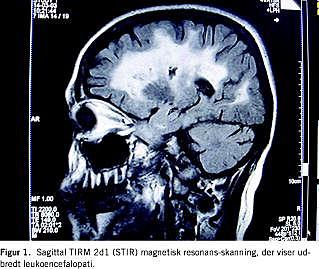

Patienten var 48 år gammel, da hun første gang havde pludseligt indsættende paræstesier i højre ansigtshalvdel, styringsbesvær i højre overekstremitet, faldtendens mod højre og begyndende sløret syn. En magnetisk resonans-skanning af cerebrum viste udbredte forandringer subkortikalt (white matter lesions) (Figur 1). Man havde mistanke om multipel sklerose (MS), men patienten ønskede ikke yderligere udredning og afbrød forløbet.

Betegnelsen CADASIL blev introduceret i 1993, hvor man fandt, at sygdommen var autosomal dominant arvelig på baggrund af en mutation på kromosom 19q12 [1]. I 1996 isoleredes mutationen til NOTCH3-receptorgen hos mennesker. Ved hudbiopsi kan der identificeres aflejring af GOM i den glatte muskulatur af små arterier og kapillærer. På MR-skanning af cerebrum ses subkortikale hvid substans-forandringer, placeret periventrikulært eller dybere subkortikalt. Disse forandringer forekommer hos alle CADASIL-patienter ofte også inden symptomdebut. Fund af GOM ved hudbiopsi er diagnostisk, men kan være falsk negativ, hvorfor det er vigtigt at supplere med MR-skanning af cerebrum og genetisk udredning [2].

Der er identificeret mere end 400 CADASIL-familier i Europa alene. Ud fra The Copenhagen Stroke Study identificerede man 80 patienter under 55 år med apopleksi. Der blev ikke fundet holdepunkter for at have mistanke om CADASIL hos en eneste af disse [4]. Til dato er der kun rapporteret om en dansk CADASIL-familie [5]. Denne sygehistorie repræsenterer således kun det andet rapporterede tilfælde af CADASIL i en dansk familie. På trods af sygdommens sjældenhed kan dette være et udtryk for underdiagnosticering. Det kan være relevant at overveje diagnosen hos en patient med tidlig TIA/apopleksi, hvor der findes familiær anamnese for dette, men i øvrigt ikke andre risikofaktorer for cerebrovaskulære lidelser. Som det fremgår af sygehistorien bør man ligeledes overveje sygdommen hos personer med kliniske og radiologiske manifestationer, der tyder på MS, men hvor spinalvæskeundersøgelse og VEP viser normale forhold. Der findes i litteraturen kun et eksempel på, at en person, som man havde mistanke om havde MS, viste sig at have CADASIL [6]. Ligesom hos vores patient fandtes der ved MR-skanning af cerebrum udbredt leukoencefalopati i blandt andet capsula externa og temporallappernes forhorn, hvilket ikke er typisk for MS.